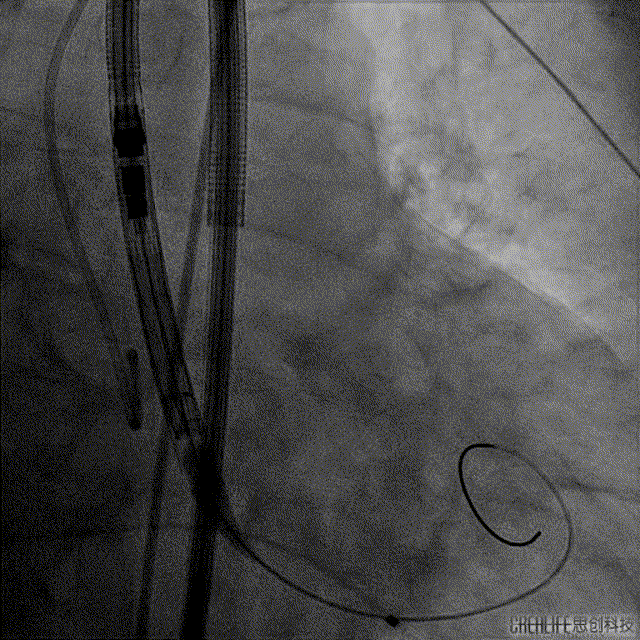

手术过程:

Numed 20mm*40mm 球囊预扩:Video 1

Venus-PowerX 26mm人工瓣膜开始定位:Video 2